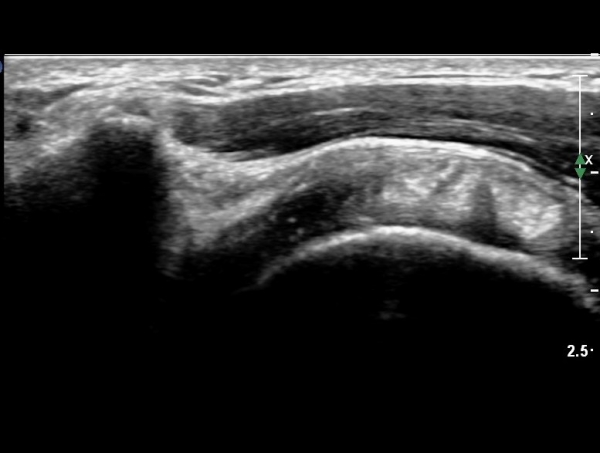

ÀÌµÎ¹Ú±Ù°Ç È¾´Ü¸é°Ë»ç¿¡¼­ °Ç ÁÖÀ§ ¼ö¾×Àú·ù µî ƯÀÌ ¼Ò°ßÀ» º¸ÀÌÁö ¾Ê¾Ò´Ù(»çÁø 1, 2)